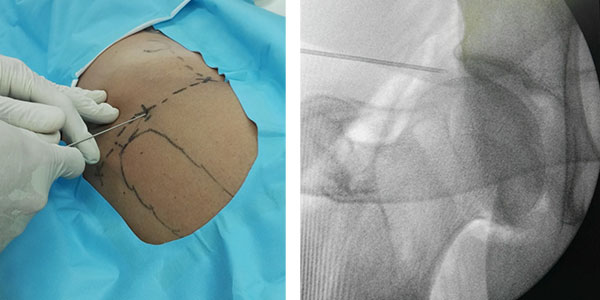

AH

cadera

Tratamientos biologicos para cadera